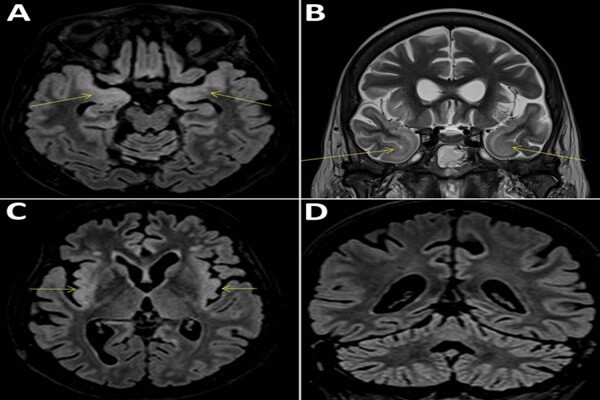

▲法國患者病逝後發現感染新型病毒,美國國家生物技術資訊中心公布其腦部磁振造影成像。(圖/翻攝自NCBI網站)

法國巴黎一名58歲婦女近期因罹患腦炎死亡,科學家對其進行新型冠狀病毒疾病檢測,意外在死者體內發現一種可能藉由蚊蟲傳播新型病毒,並將其命名為Cristoli virus。科學家表示,目前沒有跡象顯示這種病毒將導致如新冠肺炎般的公衛危機。